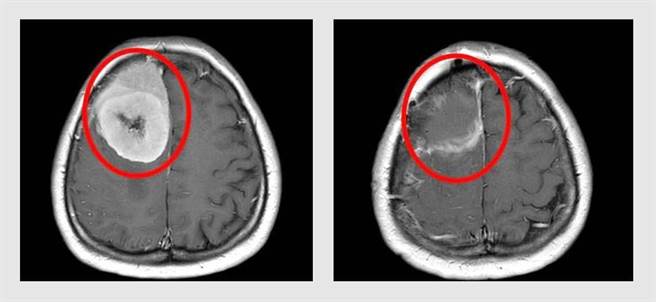

65岁吴小姐近年有头痛、头晕与视力模糊等症,误以为是眼压过高所致,进一步检查才发现脑中右侧前额叶长出1颗直径9公分巨大脑瘤。(大里仁爱医院提供/潘虹恩台中传真)

65岁吴小姐近年有头痛、头晕与视力模糊等症,一直以为是眼压过高所致,经眼科建议进一步检查才发现脑中右侧前额叶长出1颗直径9公分巨大脑瘤,医师预估极可能于半年内昏迷死亡,幸紧急安排手术摘除,顺利恢復且未留下任何神经后遗症。

由于吴小姐求诊时已出现「颅内压升高」,包含头痛、头晕和眼压升高等,经核磁共振影像发现肿瘤压迫导致脑组织出现水肿,张育铭判断,极有可能再过3个月至半年就会因为压力升高造成昏迷死亡;经医疗团队紧急安排开颅脑瘤切除手术将肿瘤切除,吴小姐顺利恢復健康,也未出现任何神经后遗症。